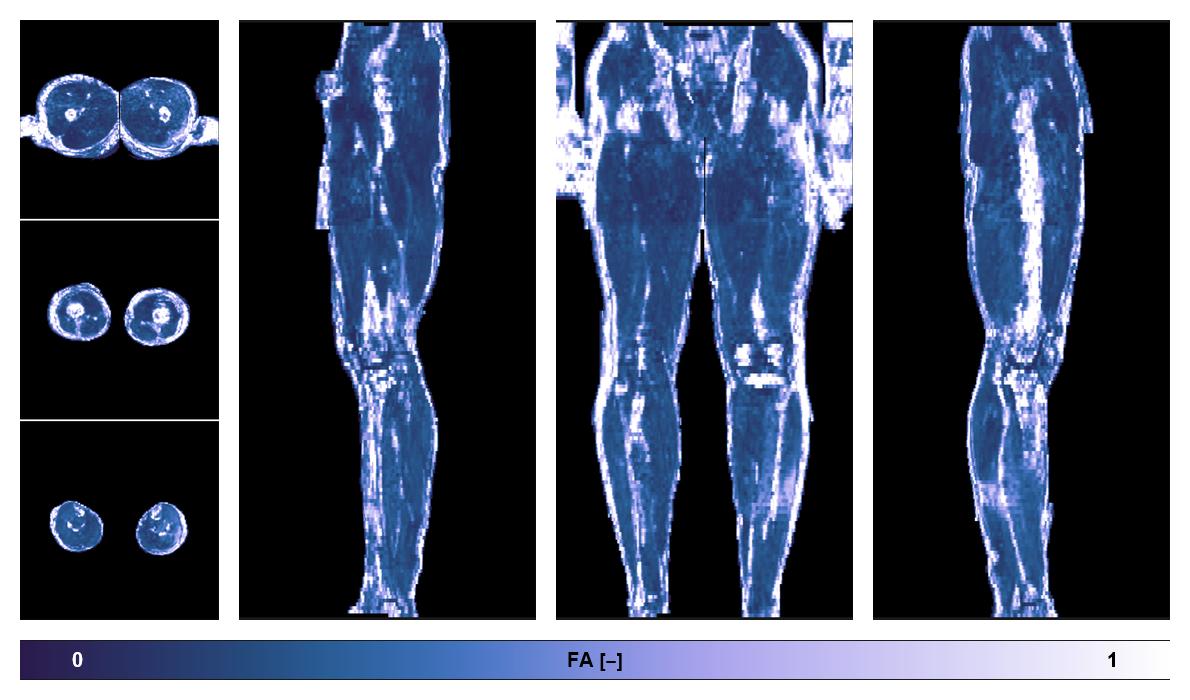

• Fractional anisotropy

IVIM corrected whole leg muscle fractional anisotropy obtained from diffusion tensor imaging.